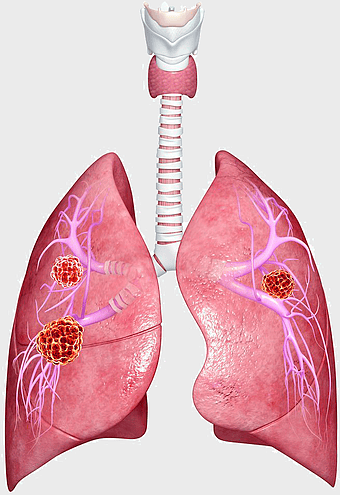

lung cancer metastasis, human lung anatomy, pulmonary carcinoma cells, prognosis of lung cancer, respiratory disease illustration, medical oncology, thoracic organ health -